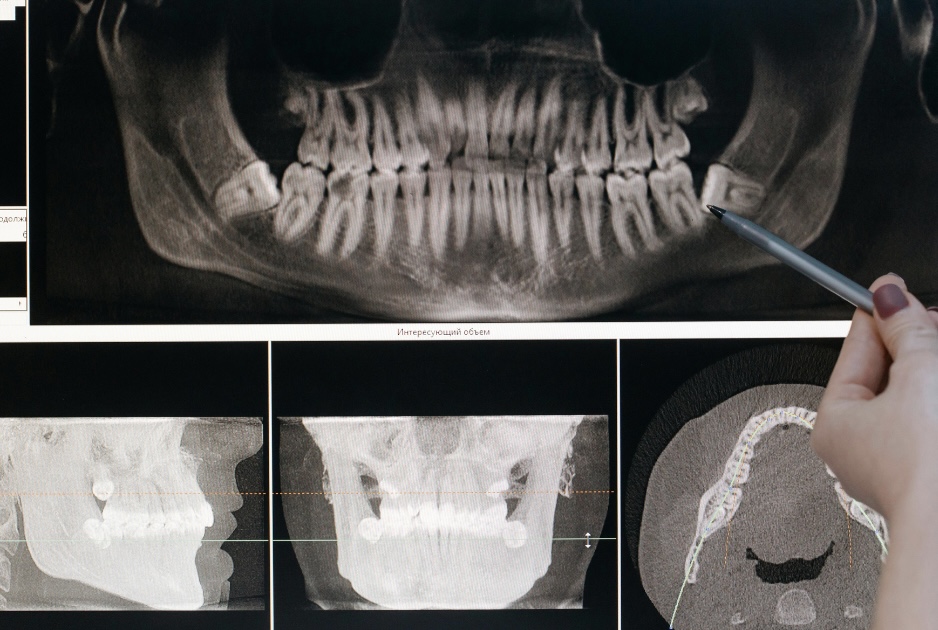

7. インプラント・入れ歯・ブリッジ

失った歯を補う治療です。患者さんの状態や希望に合わせた治療法を提案されます。

8. 口腔外科

親知らずの抜歯や顎関節症、口内炎など、口の中の外科的処置やトラブルも歯科医院で対応可能です。